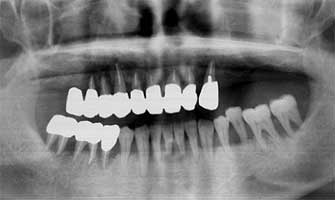

Fig. 13 Ms F 16 years old at the time of first medical examination. Woman

I regard this case to that of juvenile gum disease because there is high deposition of dental calculus and a high possibility of destruction of the alveolar bone.

Ms F 16 years old at the time of the first medical examination. Woman (Fig. 13-14)

She has undergone gingivitis treatment two years ago. However a lot of tartar of the edge of the gum was found on her teeth at the time of first medical examination. Her 5 year older sister already had a tooth in the final stage of gingivitis. Ms F therefore had the strong possibility of also developing to the final stage. Taking note of this I believed her to be of juvenile gum disease. As a result of consistently continuing to remove the tartar her tendency to develop gingivitis has not occurred even 17 years later. Even her older sister who lost a tooth to gingivitis, 16 years later has maintained and retained all other teeth.